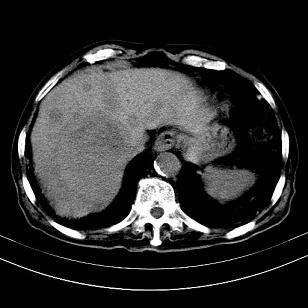

标题: CT19407:肝内还是肝外原发性肿瘤??

男,63岁,高血压病史40余年,

考虑右肝后叶肝癌伴多发肝内转移

考虑右肝后叶肝癌(部分外生)伴肝内多发性转移;右侧肾上腺区恶性肿瘤并肝转移待排。

支持肝癌肝内转移,肝硬化。

考虑右肝后叶肝癌(外生型)伴肝内转移。

考虑外生性肝癌伴肝转移

肝右叶外生性肝癌,伴肝内转移